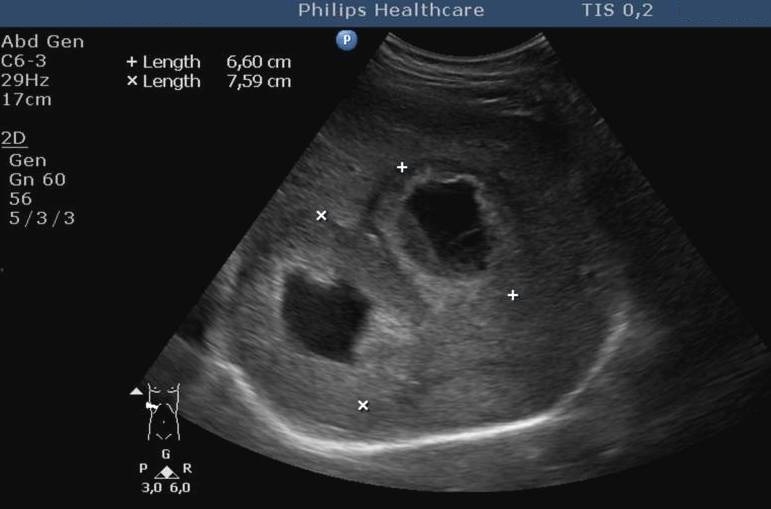

The bacteria may pile up in the biliary ducts due to the bile stasis (either by tumorous or inflammatory choledochus compression) and cholangitis can develop, associated with an abscess development later (Figure 29).

Figure 29: Abscess in the liver, US

In order to prevent it – by either endoscopically or percutaneously – the primary goal is to ensure the bile flow again, obviously completed with broad-spectrum antibiotics.

Liver abscess can develop either following the severe inflammation of the biliary ducts and the gallbladder or following a tumorous necrosis or by the spread of an external inflammation to the liver. By the help of the US, a cystic lesion can be seen with multiple internal echos containing gas bubble frequently as well. In order to determinate the further therapy, contrast enhanced CT examination can be needed, if the US imaging of the entire liver was not possible. An avascular intrahepatic lesion can be seen well on the CT with a contrast enhancing wall (sometimes multifocal as well) (Figure 30). An US or CT guided percutaneous drainage can provide a therapeutic result depending on the lesion's size and location (Figure 31).

Figure 30: Abscess in the liver, native CT

Figure 31: Abscess in the liver, US control after US guided drainage